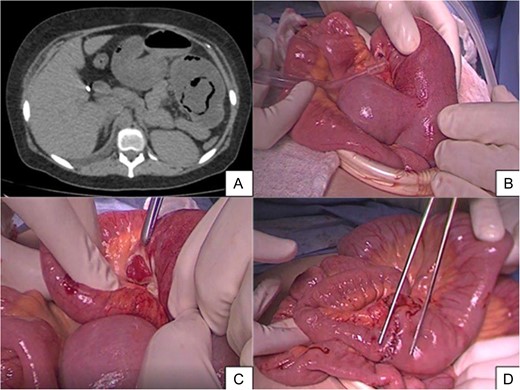

In the multi detector computed tomography, evidence was seen on the left side of an image compatible with jejuno-jejunal invagination and an aerial image in halo that could correspond to pneumatosis of the invaginated loop (Fig. 1).

(A) Axial cross-section of MSCT without intravenous contrast where an aerial image is seen in halo which could correspond to pneumatosis and parietal swelling, image compatible with jejunojejunal invagination. (B) Intraoperative finding of intussusception. (C) The presence of necrosis in intussuscepted segment. (D) Jejunojejunal anastomosis is indicated with dissection tweezers.

A pneumoperitoneum with open technique was performed. In the laparoscopic work, abundant free liquid was seen in the abdominal cavity. Later, we identified the non-dilated loop (fine loop) at the level of the ileocecal valve and we explored the small bowel from distal to proximal to the foot of the Roux-in Y where no adherences involving this were seen. At 10 cm from the foot of the Roux-in-Y, we observed a retrograded intussuscepted jejunal segment, which had an intestinal perforation of one centimeter in diameter contained by the intussuscepted block.

Not managing to reduce the invagination using blunt manual techniques, we performed a mini-laparotomy. Once the enterotomy was done and the invaginated segment was reduced, we observed necrotic intussuscepted mucosa, performing a resection and termino-terminal jejunojejunal anastomosis at 4 cm from the foot of the Roux-in-Y (Fig. 2). Upon finalizing the procedure, we once again confirmed fetal vitality (FCF: 140 bpm).